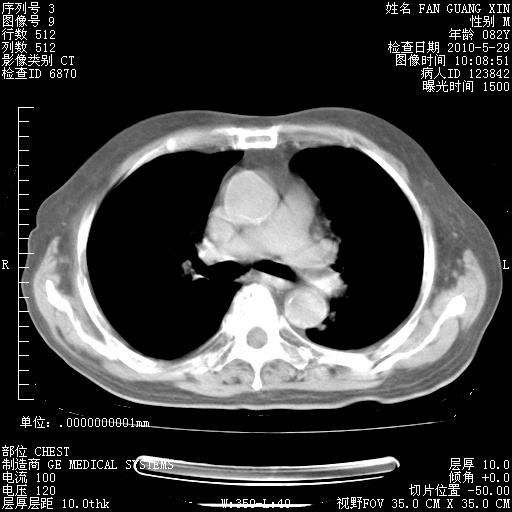

再治疗10天后的肺部CT

阅读此次胸部CT,肺间质渗出性改变较入院时有吸收。目前从体温、白细胞、中性分叶明显增高,肯定存在细菌感染(发生医院感染哦,若无消化道及泌尿系统等感染的依据,肺部感染可能大)。若你院头孢哌酮舒巴坦钠耐药率较高,同意你的方案,若48小时体温仍高,可考虑使用碳青霉稀类抗菌药物,同时可予超声雾化、注意滴数时加大液体量。白蛋白33.30g/L较低哦,需加强营养等支持治疗。